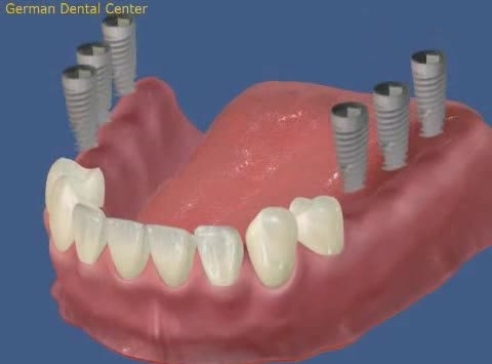

- Имплантация